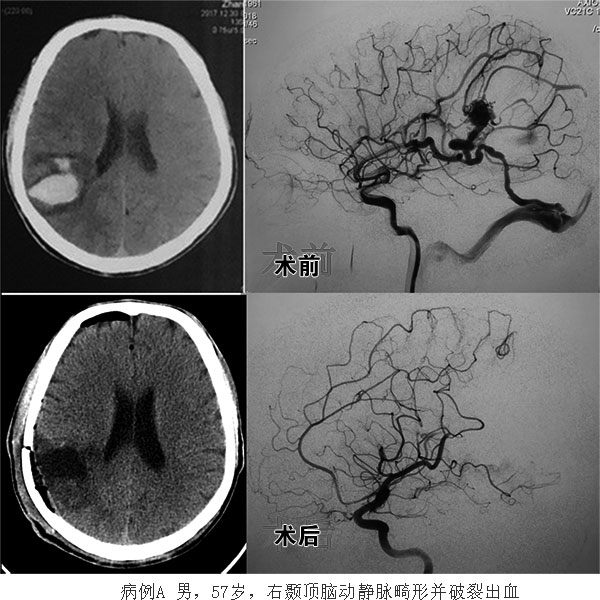

2018年伊始,神经外科在去年取得医教研可喜成绩的基础上,继续砥砺前行。复合(杂交)手术成为神经外科在新的一年继续开拓创新发展的第一个亮点。日前,在心外及主体楼手术室、神经内科、麻醉科、介入治疗室、心脏B超室等多学科的大力支持和协作下,神经外科成功完成了一例“一站式复合手术治疗脑动静脉畸形并清除颅内血肿”及“应用复合手术开通慢性颈动脉闭塞一例”。这也是我院首次独立开展此项技术,脑动静脉畸形一站式复合手术由林晓风主任医师和陈光忠主任医师主刀完成;慢性颈动脉闭塞复合手术开通由神经外科陈光忠主任医师和神经内科代成波副主任医师主刀完成。两例手术均取得圆满成功。

脑动静脉畸形与颈动脉慢性闭塞是脑血管病中难以治疗的两种疾病。脑动静脉畸形被称为脑血管病中的“九头蛇”魔兽。治疗方法虽然有显微外科手术、血管内介入和立体定向放射外科治疗,但无论哪一种治疗方式均难以达到理想的治愈效果,往往需要多次治疗。对患者及家人带来严重的精神和经济上的负担。而一站式复合手术则大大提高了一次性治愈脑动静脉畸形的几率。可以简单的理解为:在进行显微外科手术切除的同时,进行脑血管造影或辅助栓塞,发现哪儿有残留病灶可以定向清除,直至完全切除。